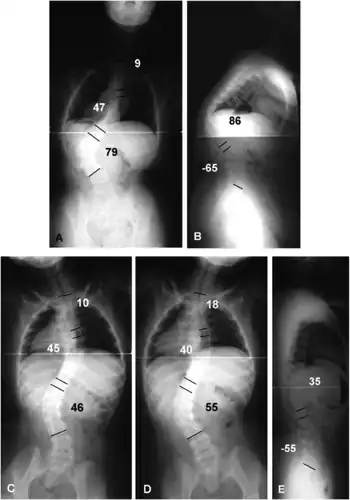

- Joint laxity (scoliosis)